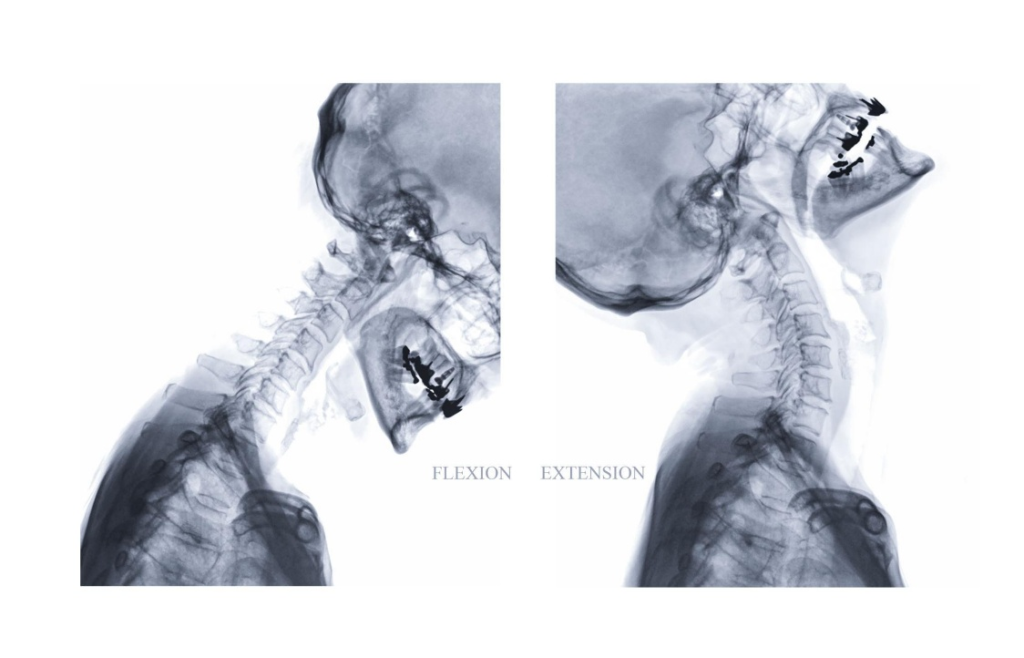

Whiplash & Ligament Instability Assessment

Targeted evaluation of cervical and spinal ligament injury and instability patterns that contribute to chronic pain, early degeneration, and neurologic symptoms.

Digital X-Ray & PostureRay® Biomechanical Analysis

On-site digital radiography integrated with PostureRay® delivers precise biomechanical measurements of spinal alignment, motion, and structural deviation—providing objective data to identify injury, guide treatment, and document measurable correction.